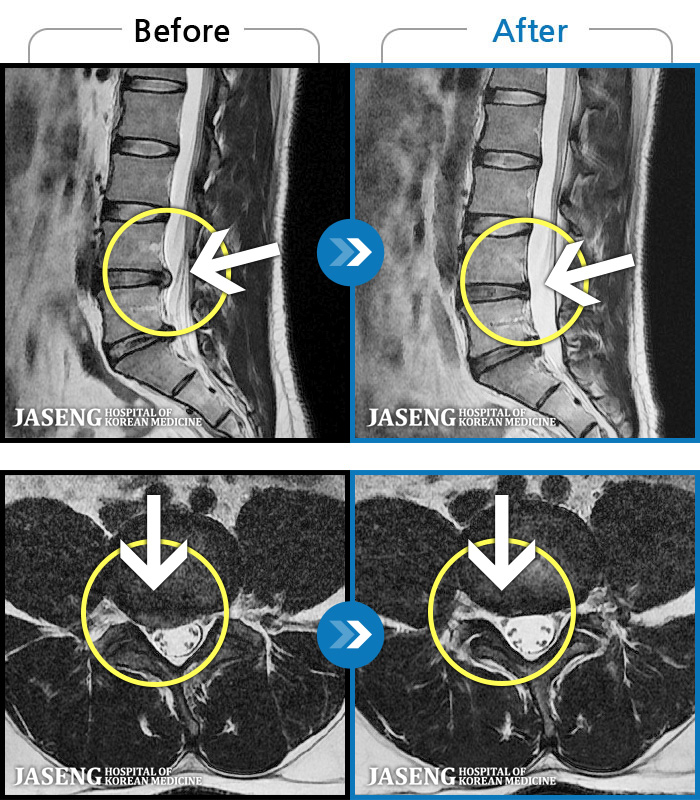

MRI ġ

1,240 MRI ũ ʸ Ȯϼ.